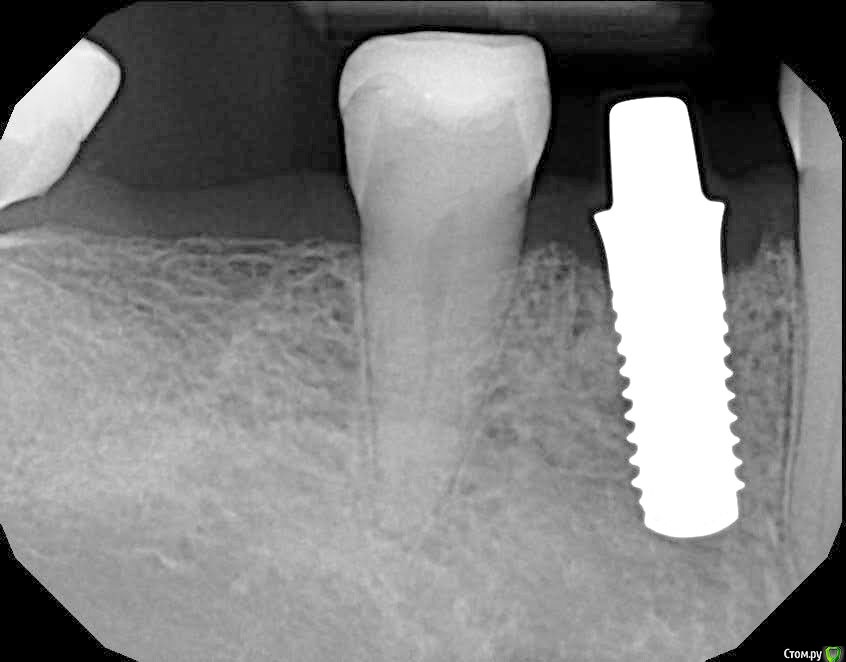

Astronaft Опубликовано 24 января, 2021 Поделиться Опубликовано 24 января, 2021 (изменено) Одиночный цирнокиевый имплантат и расщепление без графта. Пациентка:тонкая хрупкая женщина 55 лет, сконцентрированная на своем здоровье, в некоторой мере мнительная.всегда тяжелые заживления после удалений (по опросам)есть результаты Клиффорд теста (такая книжка под 200 страниц с in vitro аллерго-пробами на все известные материалы) Поставленная цель:только цирконий Мне было интересно найти вариант найболее приемленый пациентке и мне. С минимом хирургического риска и риском сожаления пациентки про выбор костного материала. Во-первых, я не использую аллографты - философски, чужие протеины, неприятный запах - просто основываясь на своем мнении.Во-вторых, мнительные пациенты склонны "пойти и почитать" до или потом и как следствие внушить себе вещи которых может и не было. Но по скольку мысль материальна... Все обсудил заранее.План: ридж сплит (расщепление), имплантат без графта, свободный СТ графт; если случается вестибулярная рецессия - пилим зирконий во рту. Ридж сплит сделан пьезотомом - крестальный и вертикальные пропилы на глубины около 8-10мм.Пилотное сверло.Развдвинул кость остеотомами от 1.6мм до 3.5мм в диаметре.Очень мягкая кость - напомнила мегкую максиллу плотности ногтевой пластинки вестибулярно.Имплант встал легко, но торк 40нсм. СТ графт из области 18. Деэпителизирую скальпелем уже потом. Тут интересно отметить, что я перестал боятся ошметков эпителия.Пончо сверху имплантата (а-ля шашлык Карлоса).Швы. PTFE всегда хорош. 12 недель.Красивая десна.Периотест -5.8 - отличный результат.Оттиск. Циркониевая коронка симметричная другой стороне. Изменено 24 января, 2021 пользователем Astronaft 19 Ссылка на комментарий

Astronaft Опубликовано 25 января, 2021 Автор Поделиться Опубликовано 25 января, 2021 Спасибо.День операции, 12 недель, день цементировки. 3 1 Ссылка на комментарий